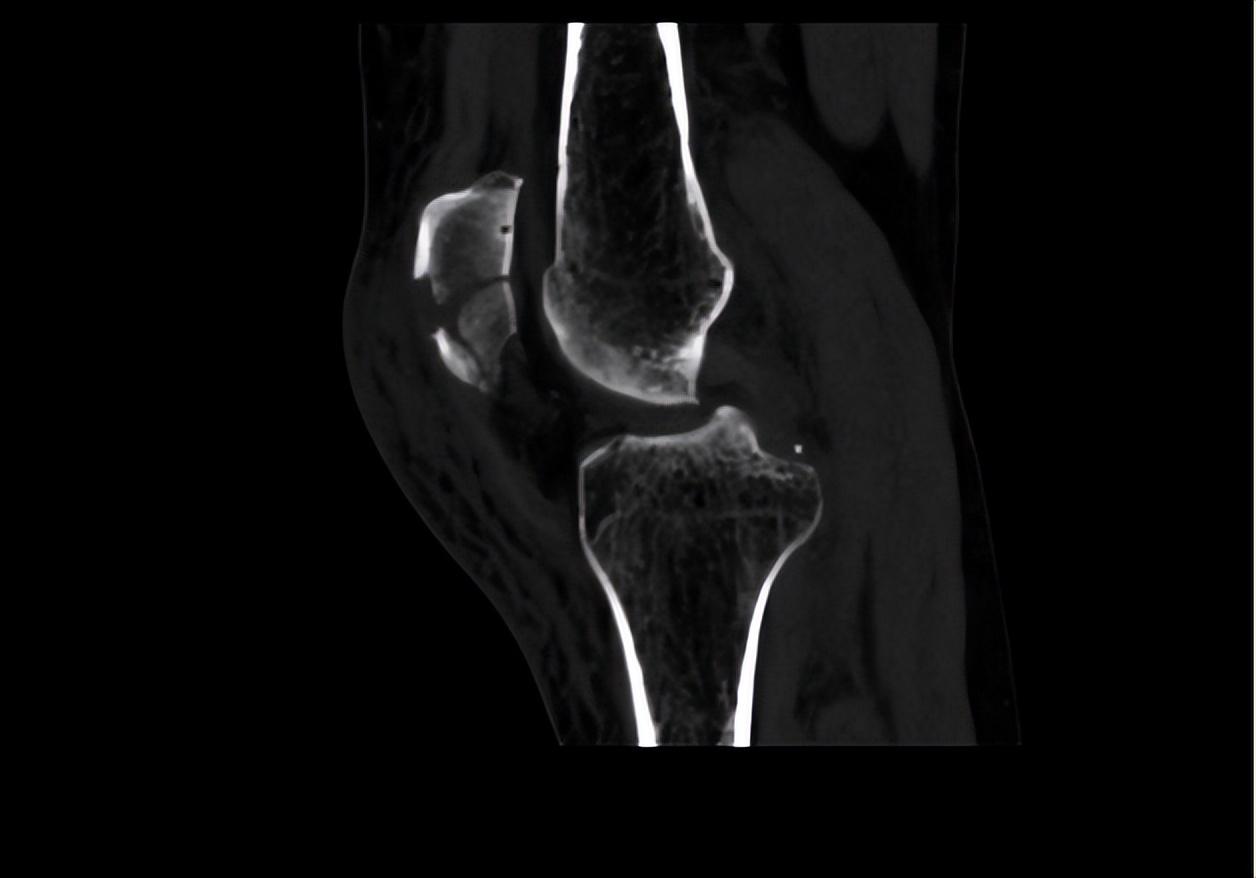

二、調(diào)節(jié)過(guò)程針對(duì)患者目前左髕骨骨折的情況,首要調(diào)節(jié)為進(jìn)行手術(shù)調(diào)節(jié),所以待患者入院后,我立刻給她開(kāi)了相關(guān)檢查,以排除手術(shù)禁忌。完善血常規(guī)、肝腎功、電解質(zhì)、大小便常規(guī)、凝血功能、輸血前檢查等均未見(jiàn)異常。同時(shí)我也讓患者完善了心電圖、彩超、CT檢查和X影像學(xué)檢查。雙下肢彩超提示:雙下肢動(dòng)脈輕度輕度粥樣硬化。左膝關(guān)節(jié)平掃CT+二維、三維重建顯示:髕骨骨折,少量關(guān)節(jié)積液。心電圖未見(jiàn)異常。